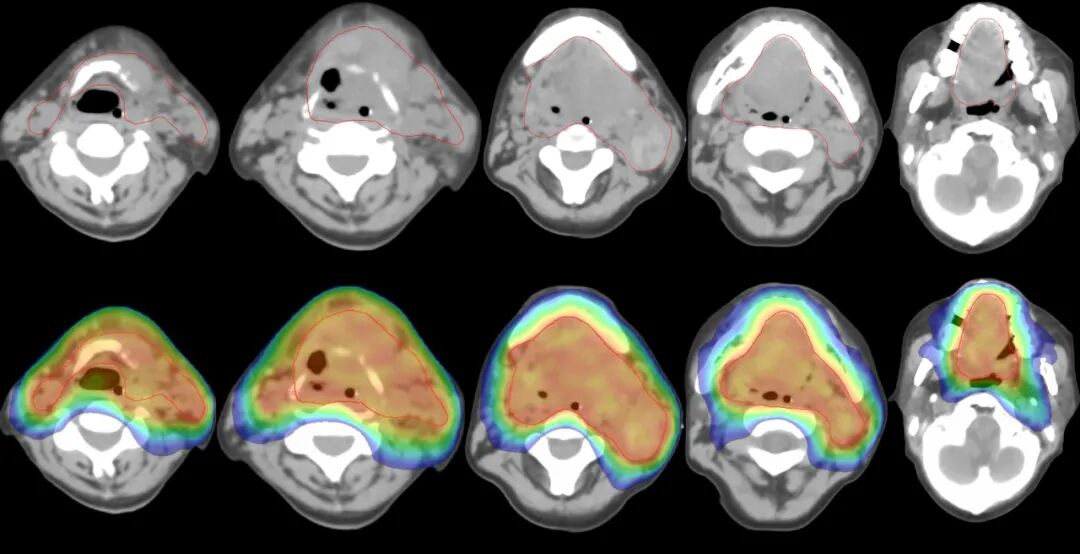

1周后患者生命體征基本恢復(fù),轉(zhuǎn)回放射治療科立即開始放射治療。采用全影像引導(dǎo)的高速容積旋轉(zhuǎn)調(diào)強(qiáng)放射治療技術(shù),單次治療時(shí)間僅2分鐘,高速治療確?;颊呖梢韵鄬?duì)安全地完成治療,且治療中耐受性良好。此外,由于患者口腔腫物巨大,面部及下頜部已經(jīng)變形,無法給予常規(guī)應(yīng)用熱縮膜定位。對(duì)于此類極為特殊嚴(yán)重的患者,IGRT全影像引導(dǎo)放療發(fā)揮了巨大作用!確保了患者每次治療時(shí)位置的精確性,確保精準(zhǔn)照射。

圖注:放射治療靶區(qū)及劑量分布圖。上排為腫瘤區(qū)域(紅線內(nèi)),可見腫瘤范圍巨大, 完全侵占整個(gè)口腔、口咽腔、咽喉腔;雙側(cè)頸部可見轉(zhuǎn)移淋巴結(jié);下排為放射治療劑量分布,可見聚焦照射,周邊劑量快速跌落,周圍組織受到良好保護(hù)。